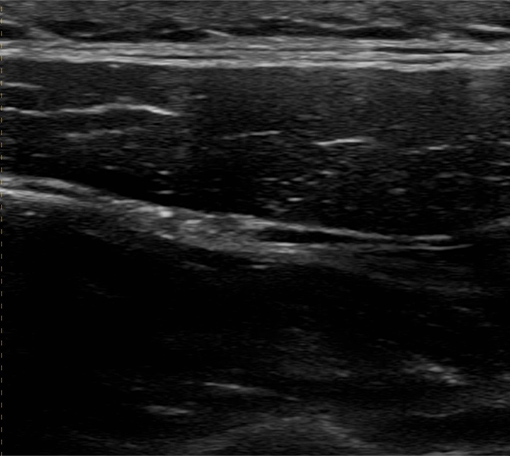

肩こりへの超音波エコーガイド下鍼

肩周囲の筋肉や神経をエコーで確認し、こりや痛みの原因部位へ的確に鍼を行います。深部の慢性肩こりにも対応します。